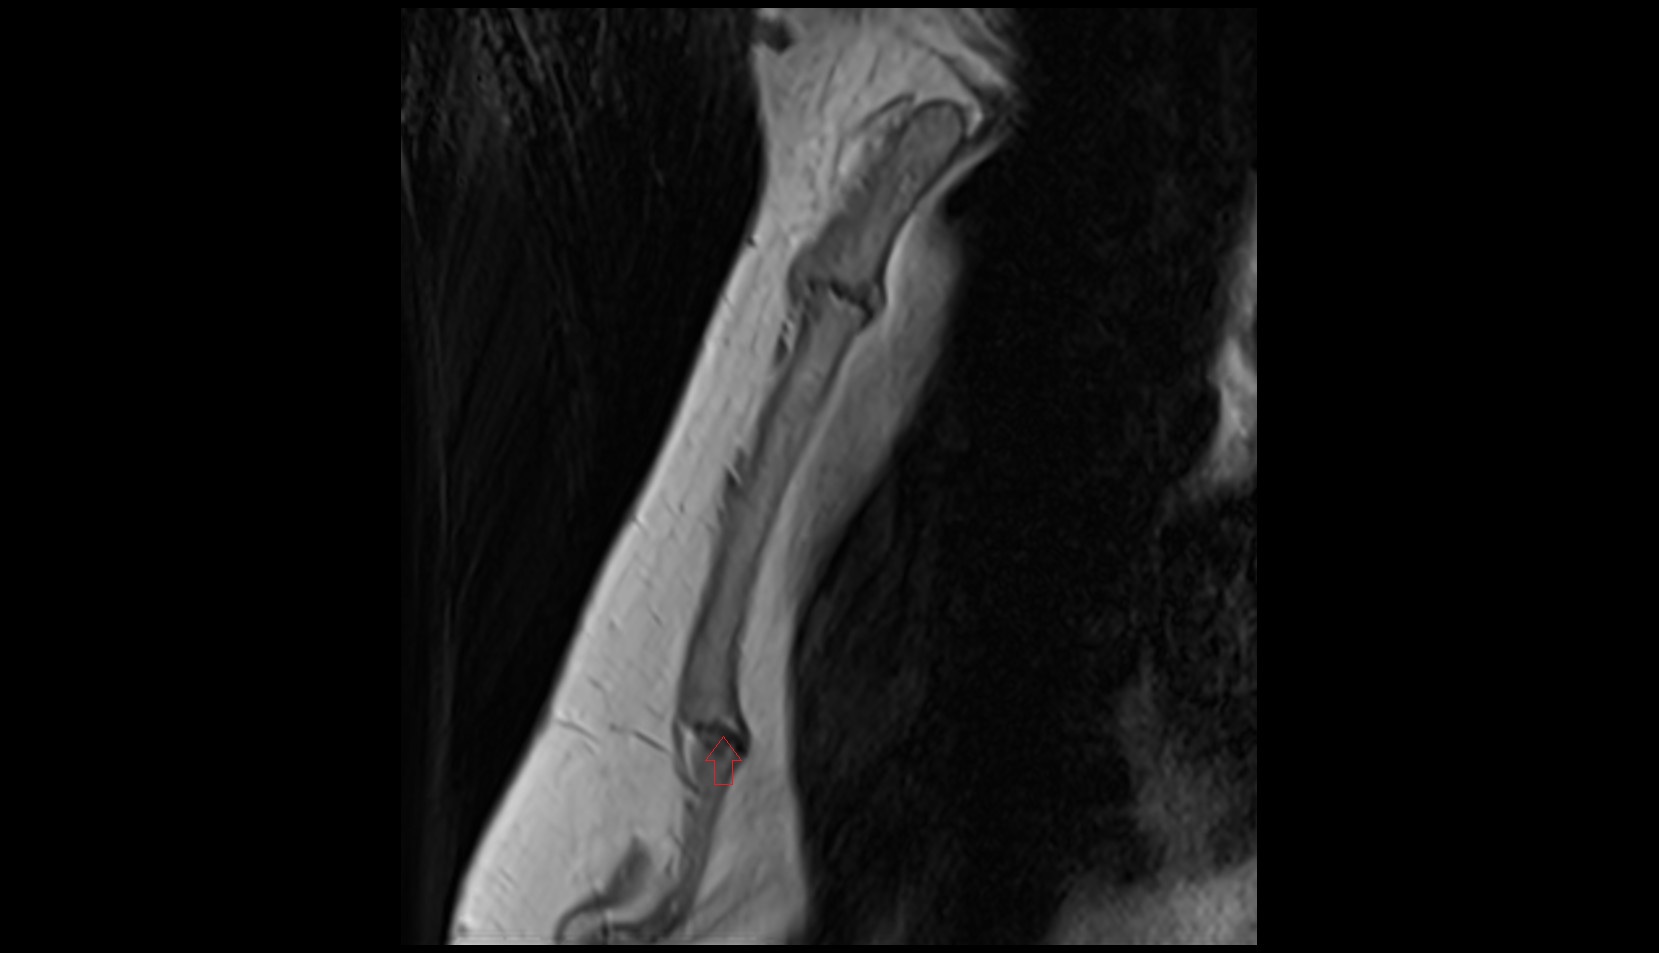

- Radius

- Ulna

- Body of radius

- Elbow joint

- Biceps brachii tendon (distal)

- Triceps brachii tendon

- Joint capsule of elbow